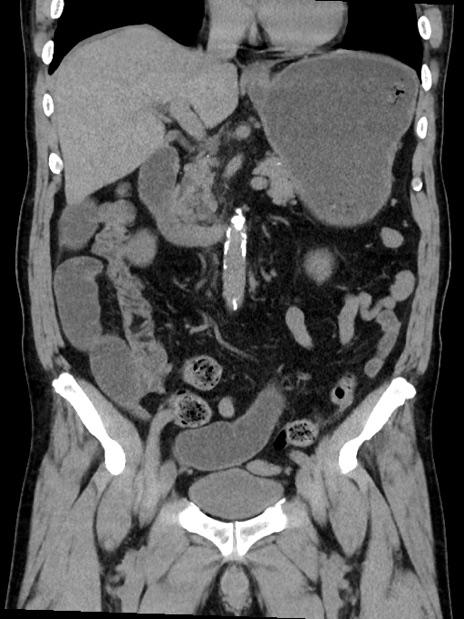

症例35(冠状断像)

症例

【症例】70歳代 男性

【主訴】腹部膨満、嘔吐

【現病歴】昨日より腹部膨満感出現。本日増悪し、仙痛出現。嘔吐あり、受診。

【既往歴】糖尿病、胆摘後

【身体所見】BP 149/80mmHg、HR 74/min、BT 35.9℃、腹部:膨満、軟、圧痛なし。腸雑音減弱あり。上腹部正中切開瘢痕あり。

【データ】WBC 13500、CRP 1.72